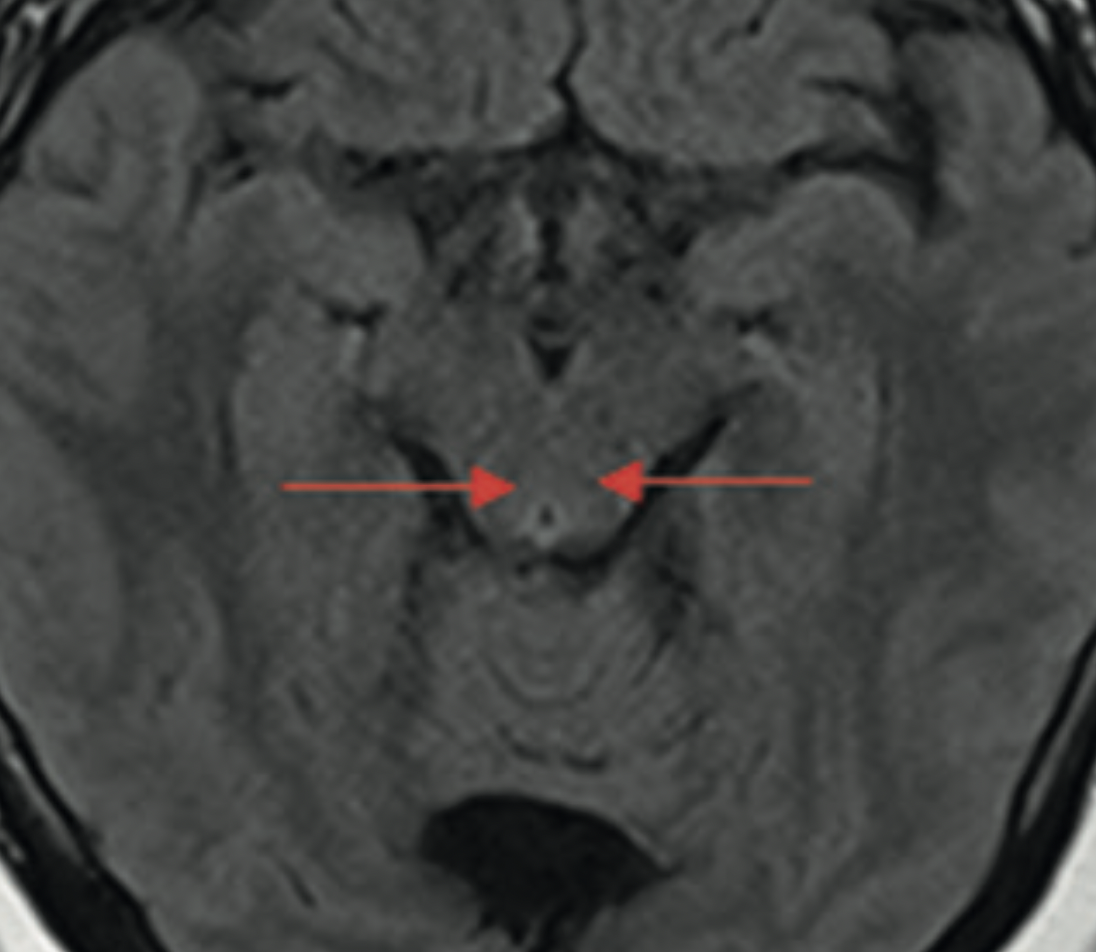

Materiales y métodos: Mujer de 23 años obesa sometida a BPGL, que desde el cuarto día postoperatorio presenta náuseas, tos, sialorrea, discomfort abdominal e irritabilidad. El estudio imagenológico y endoscópico descartan complicaciones quirúrgicas. Se sospecha una EW. Una resonancia magnética cerebral resulta normal. Sin embargo, tras una carga de tiamina resuelven los síntomas.

Resultados y discusión: Los vómitos, la cirugía y la fisiológicamente limitada reserva de B1 determinaron una aparición precoz de EW, que típicamente ocurre entre las 4 y 12 semanas en CB. La sintomatología clásica y sus hallazgos imagenológicos se presentan en la minoría de los pacientes. La EW es una complicación infrecuente, pero potencialmente grave en CB, incluso con daño irreversible de la memoria. El volumen creciente de la CB ha aumentado su incidencia. Una adecuada suplementación y sospecha diagnóstica son fundamentales para su prevención y tratamiento precoz.